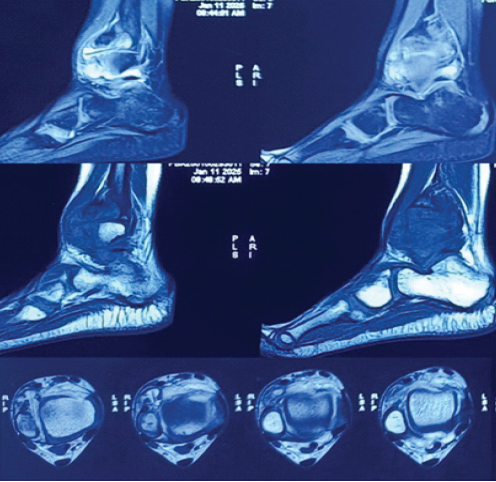

Review of MRI at our institute showed a T2 hyperintense lesion at the lower end of the fibula reaching up to the cortex medially with cortical irregularity. The lesion was surrounded by marrow oedema (Fig. 3). It was possible to see mild joint effusion, synovial effusion, and synovial hypertrophy. The diagnosis of TB was not definitive.

Figure 3: Sections of magnetic resonance imaging showing a foreign body just anterior to the syndesmosis and ankle joint effusion.